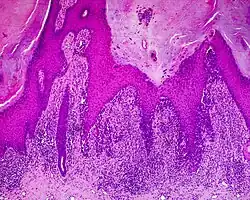

Histology

The main characteristic of acral lentiginous melanoma is continuous proliferation of atypical melanocytes at the dermoepidermal junction.[15] Other histological signs of acral lentiginous melanoma include dermal invasion and desmoplasia.[16]

According to Scolyer et al.,[17] ALM "is usually characterized in its earliest recognisable form as single atypical melanocytes scattered along the junctional epidermal layer".

- Acral lentiginous melanoma (ALM)